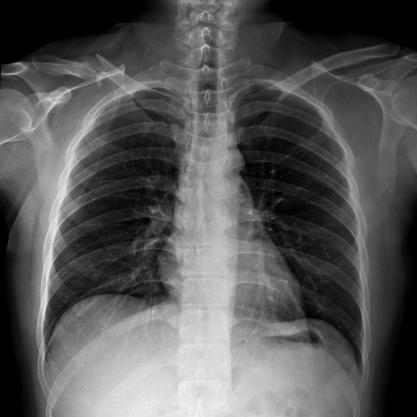

滿足不同身高的受檢者快速地進行胸片的靜態及動態檢查,適合大規模體檢。

SID可拉伸至1.8米,滿足標準胸片、職業性塵肺病檢查等特殊需求。